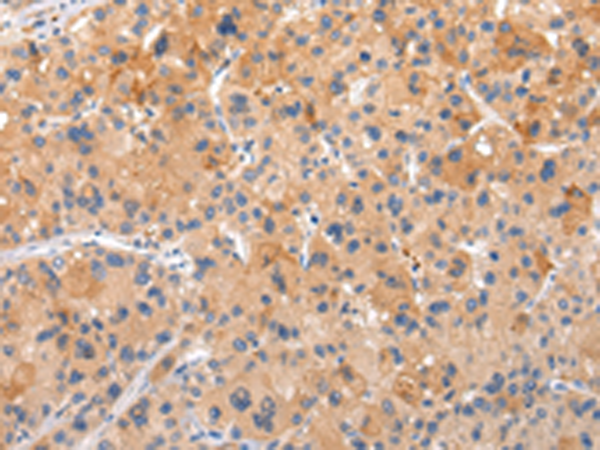

分类: 科研抗体货号: P12486别名: CDX3; CDX-3; CDX2/AS应用: WB,IHC反应种属: Human, Mouse